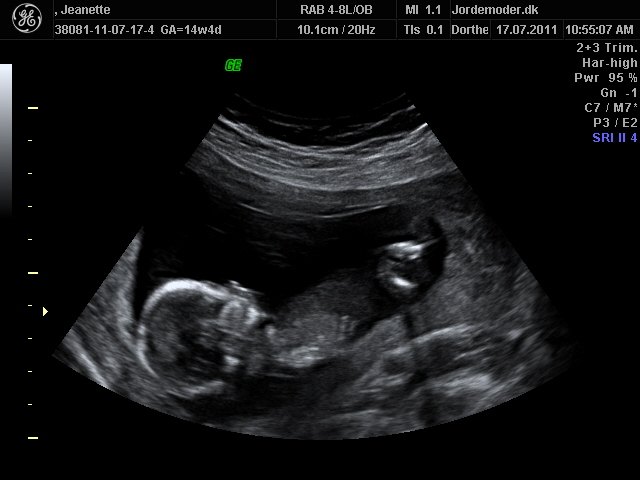

Så kom dagen for kønsscanningen.....

Svaret blev.... dam dam dam dam... ET BARN.. griner...

Ej hende der skulle scanne var ikke sikker på barnets køn, så vi skal op til kønsscanning igen om nogle dage.... men men men dejligt nok, for så får vi vores lille skat at se igen på skærmen....

Vedhæftede fotos (klik for at se i fuld størrelse)